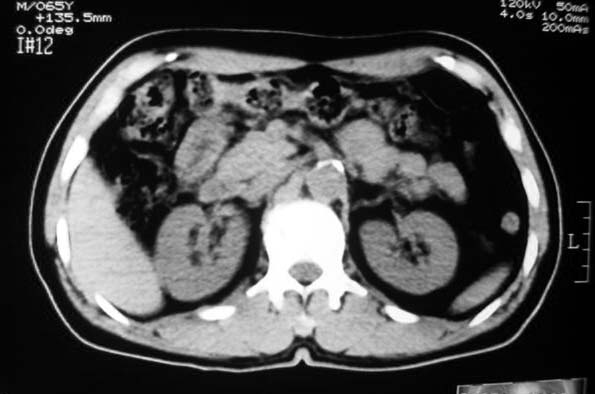

定位:病灶位于胃腔外,大弯侧后下方.

特征:实质性肿物,边界清楚,内见低密度影,明显压迫胃壁,并形成切迹.

考虑:脾门淋巴瘤或间质瘤.

胃大弯侧,胃底与胃体交界处可见一圆形软组织肿块影,边缘较光整,内部密度较均匀

考虑:胃平滑肌瘤

考虑:脾门淋巴瘤或间质瘤

考虑:胃间质瘤?息肉?

病灶起源于胃壁向腔内外突出,边缘光整,内可见片状低密度区,考虑胃壁非上皮性肿瘤可能性大

病灶起源于胃壁向腔内外突出,边缘光整,内可见片状低密度区,考虑间质瘤可能性大,建议增强扫描。